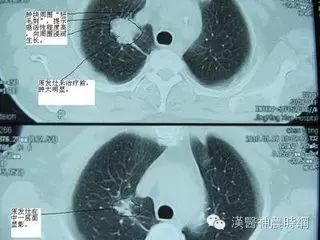

腺癌这种类型和吸烟关系最小,占肺原发肿瘤的40%。常位于肺的周边部,还累及胸膜并形成相关的疤痕圈和胸腔积液。周围型腺癌发生在和结核或梗死或其他损害相关的疤痕区的理论已经有很长时间了。疤痕癌的概念提示癌前病变上皮在疤痕区发生改变引起癌。然而一些研究者则提出疤痕继发于癌。